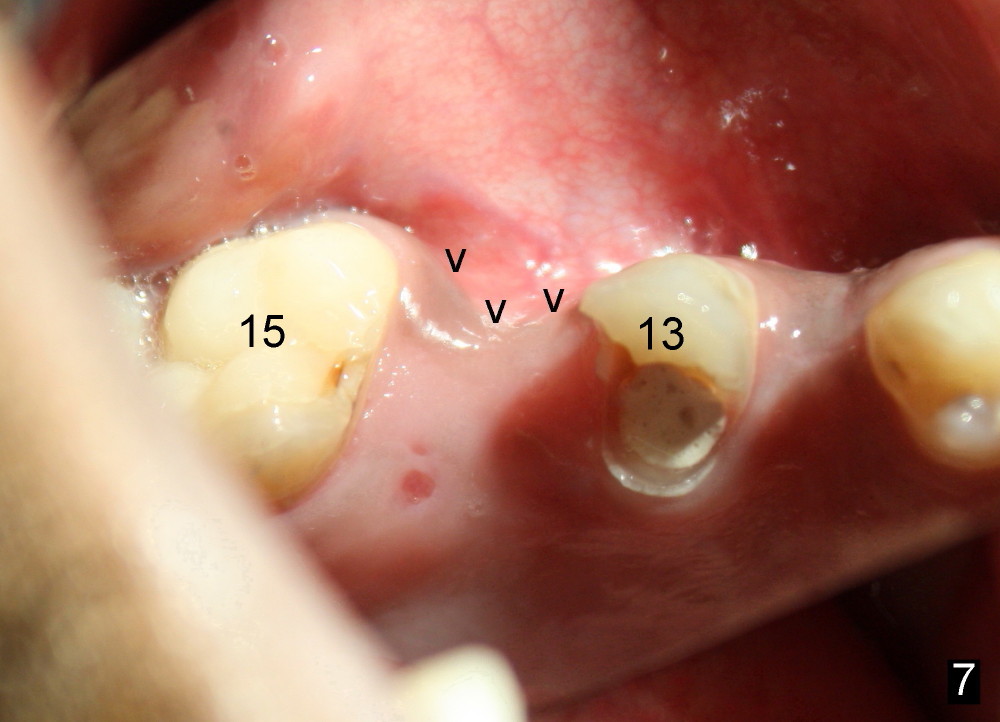

In addition to pain associated with dry socket, the buccal plate is atrophic 10 months post extraction (Fig.7 arrowheads, 1st case). A smaller implant (6x17 mm) is placed after bone expansion (Fig.8, bone appears to be soft). The buccal plate morphology improves immediately (Fig.9) and 6 days (Fig.10) post implantation and bone expansion. The patient returns for follow up 7 months postop; the implant appears to have osteointegrated (Fig.11). The implant has been restored for 3 months (09/11/2014).